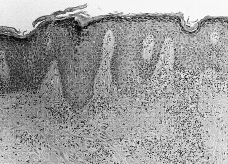

La histología (Figs. 4, 5, 6 y 7) correspondía a un patrón liquenoide en tres de ellos, a una dermatitis espongiótica en otro y una hiperplasia pseudoepiteliomatosa en el restante (tabla II). Realizadas las pruebas epicutáneas, a las pacientes 1 y 2 con la batería estándar del GEIDC, batería de colorantes textiles, mercurio, cadmio y la tinta que ellas aportaron, y al 4 únicamente con su tinta, encontramos una positividad a la tinta la paciente número 2 (++/+++). Hemos realizado 25 controles con dicha tinta, encontrando sólo una positividad, por lo que interpretamos que la reacción de nuestra paciente no es irritativa.

FIG. 5.--Paciente número 3. Se aprecia una dermatitis de interfase con exocitosis y abundante infiltrado inflamatorio superficial y profundo. Se puede ver pigmento tanto intra como extracelular.